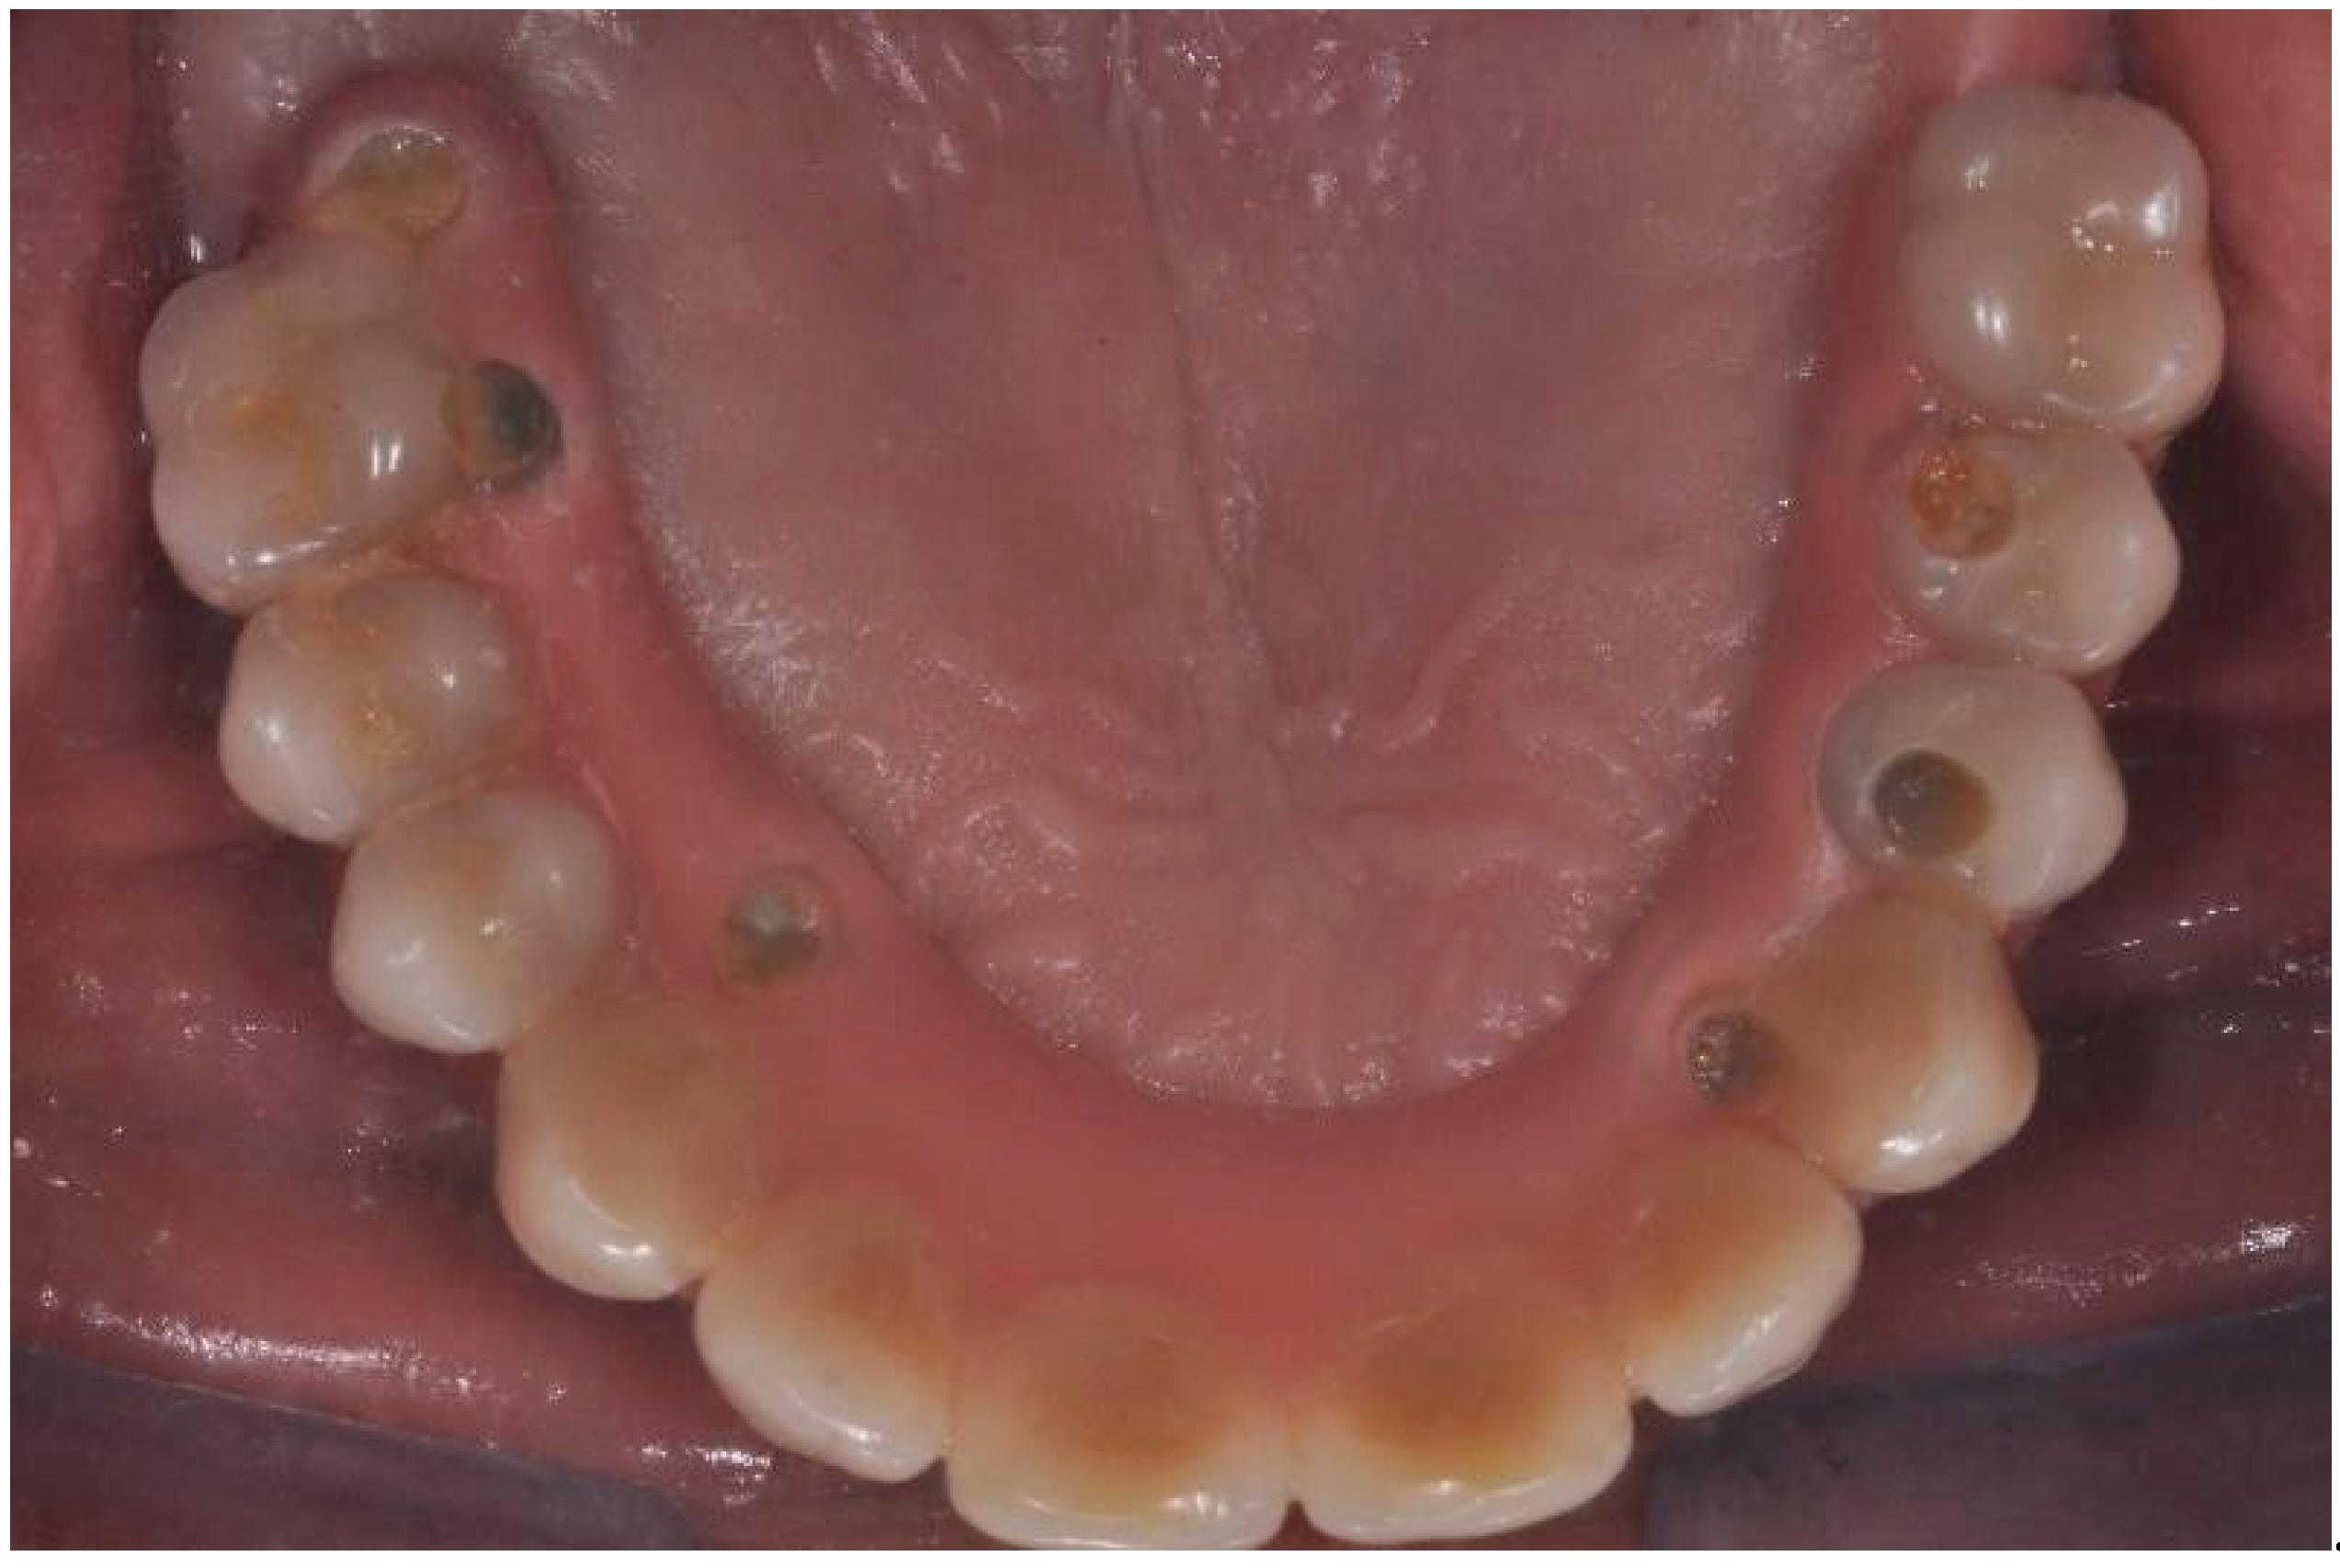

| Flanagan D. et al. [23] | J Oral Implantol | 2015 | clinical and radiographic: full-mouth radiographic series, panoramic and a bimaxillary cone beam computerized scan and mounted study casts | -One patient | Subject of 34 yo male; severely carious teeth and associated chronic abscesses (kidney transplant delayed) Comorbidities: IgA nephropathy, tabagism, hypertension and secondary hyperparathyroidism. Hemodialysis three times weekly. Ph. Therapy: Nephrocaps vitamin (B) supplement, amlodepine, besylate, cinacalcet, metoprolol, paroxetine. Bilateral compound ulnar and radial fractures, 2 blood transfusions. | Successfully treated with dental implant-supported fixed prostheses: fixed bimaxillary porcelain fused to metal implant-supported complete dentures |

| Hernández G. et al. [26] | Clin Oral Impl Res | 2019 | AI, MCI and TP reduction in mineral density of the cortical and trabecular bone in CRF patients and more severely in patients under haemodialysis compared to peritoneal dialysis | 1 IF in T | Mean follow-up of 116.8 months range from 84 to 192 months) | Renal transplant patients, are subjected pharmacological immunosuppression therapy |

| Flanagan D. et al. [23] | J Oral Implantol | 2015 | -Implant treatment for patients with IgA nephropathy (secondary hyperparathyroidism and osteodystrophy) may be successful. -Appropriate calcium therapy is important serum calcium to prevent inappropriate bone remodeling | 2 years | Long-term dialysis patient with end-stage renal disease (ESRD)also referred to as chronic kidney disease (CKD) due to IgA nephropathy complicated by severe secondary hyperparathyroidism and renal osteodystrophy | |